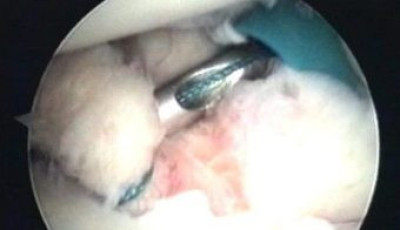

Se está realizando la anudación con la ayuda de un instrumento metálico (knot pusher)